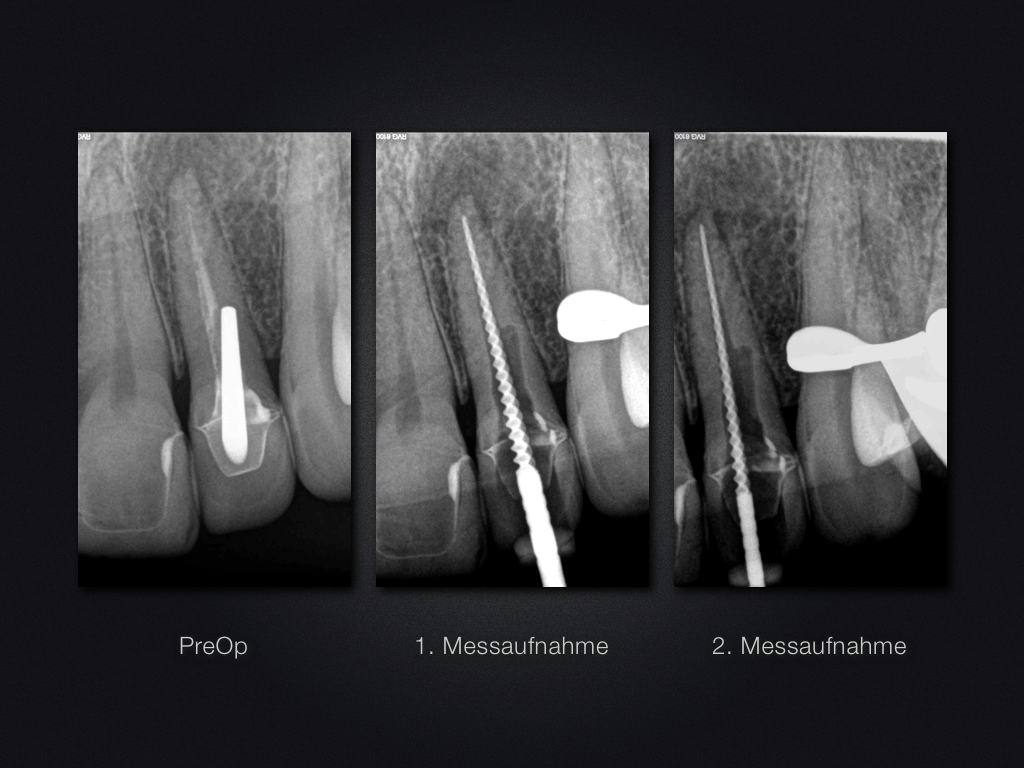

22D.001

Unverhofft kommt oft